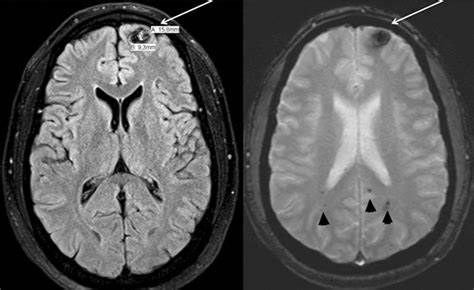

脑海绵状血管瘤是发生在整个中枢神经系统的血管造影隐匿性低流量血管畸形。病理上,脑海绵状血管瘤由内皮细胞浸润的空洞组成,缺乏适当形成的紧密连接。这些病变的形成、生长和出血,以及周围因出血或血管泄漏而形成的铁质沉积,是本病的临床表现。脑出血(ICH)、癫痫(伴有或不伴有出血)、局灶性神经功能缺损(FND)而无出血或偶然发现可引起临床注意。出血性脑海绵状血管瘤的预后比癫痫或FND更差。

脑海绵状血管瘤可以是偶发的、单一的病变,也可能是家族性的。家族型的患者有多个病变,每个病变都有独自的生长或出血风险。散发的脑海绵状血管瘤通常是单一的病变,可能是由于血管环境的改变,因为经常发现发育性静脉异常(DVA)。一些学者推测,相关的DVA不仅在脑海绵状血管瘤的发病机制中起作用,还可能影响出血的风险。也就是说,如果DVA胚根血栓形成,可能会增加脑海绵状血管瘤的流出阻力,导致出血。如果后一种理论是正确的,那么在散发性和家族性出血风险的影响因素上可能存在差异。